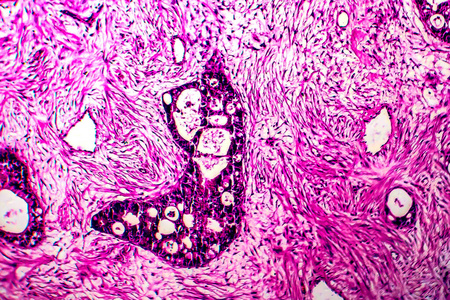

宫颈癌时看到的切片

图片尺寸500x318